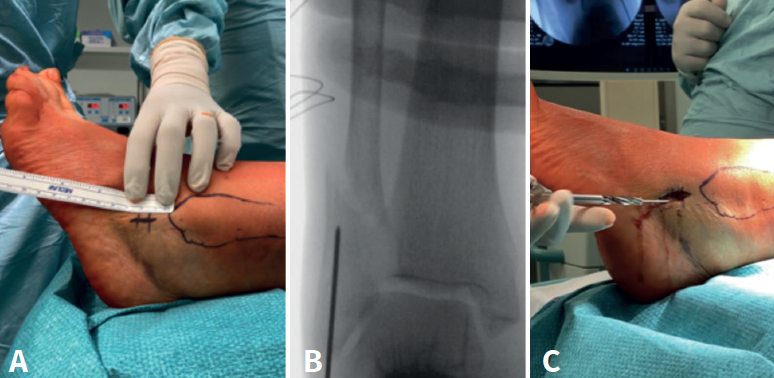

Así pues, hace unas décadas, el aumento de las complicaciones en la población anciana con la RAFI planteó la cuestión de buscar otras alternativas. Teniendo en cuenta las complicaciones derivadas del tratamiento conservador con yeso (desplazamiento secundario y mal unión/pseudoartrosis, principalmente), se comenzaron a realizar estudios sobre técnicas mínimamente invasivas, entre ellas el clavo de peroné intramedular, que requiere de incisiones más pequeñas y presenta un implante de más bajo perfil (Figuras 2 y 3).